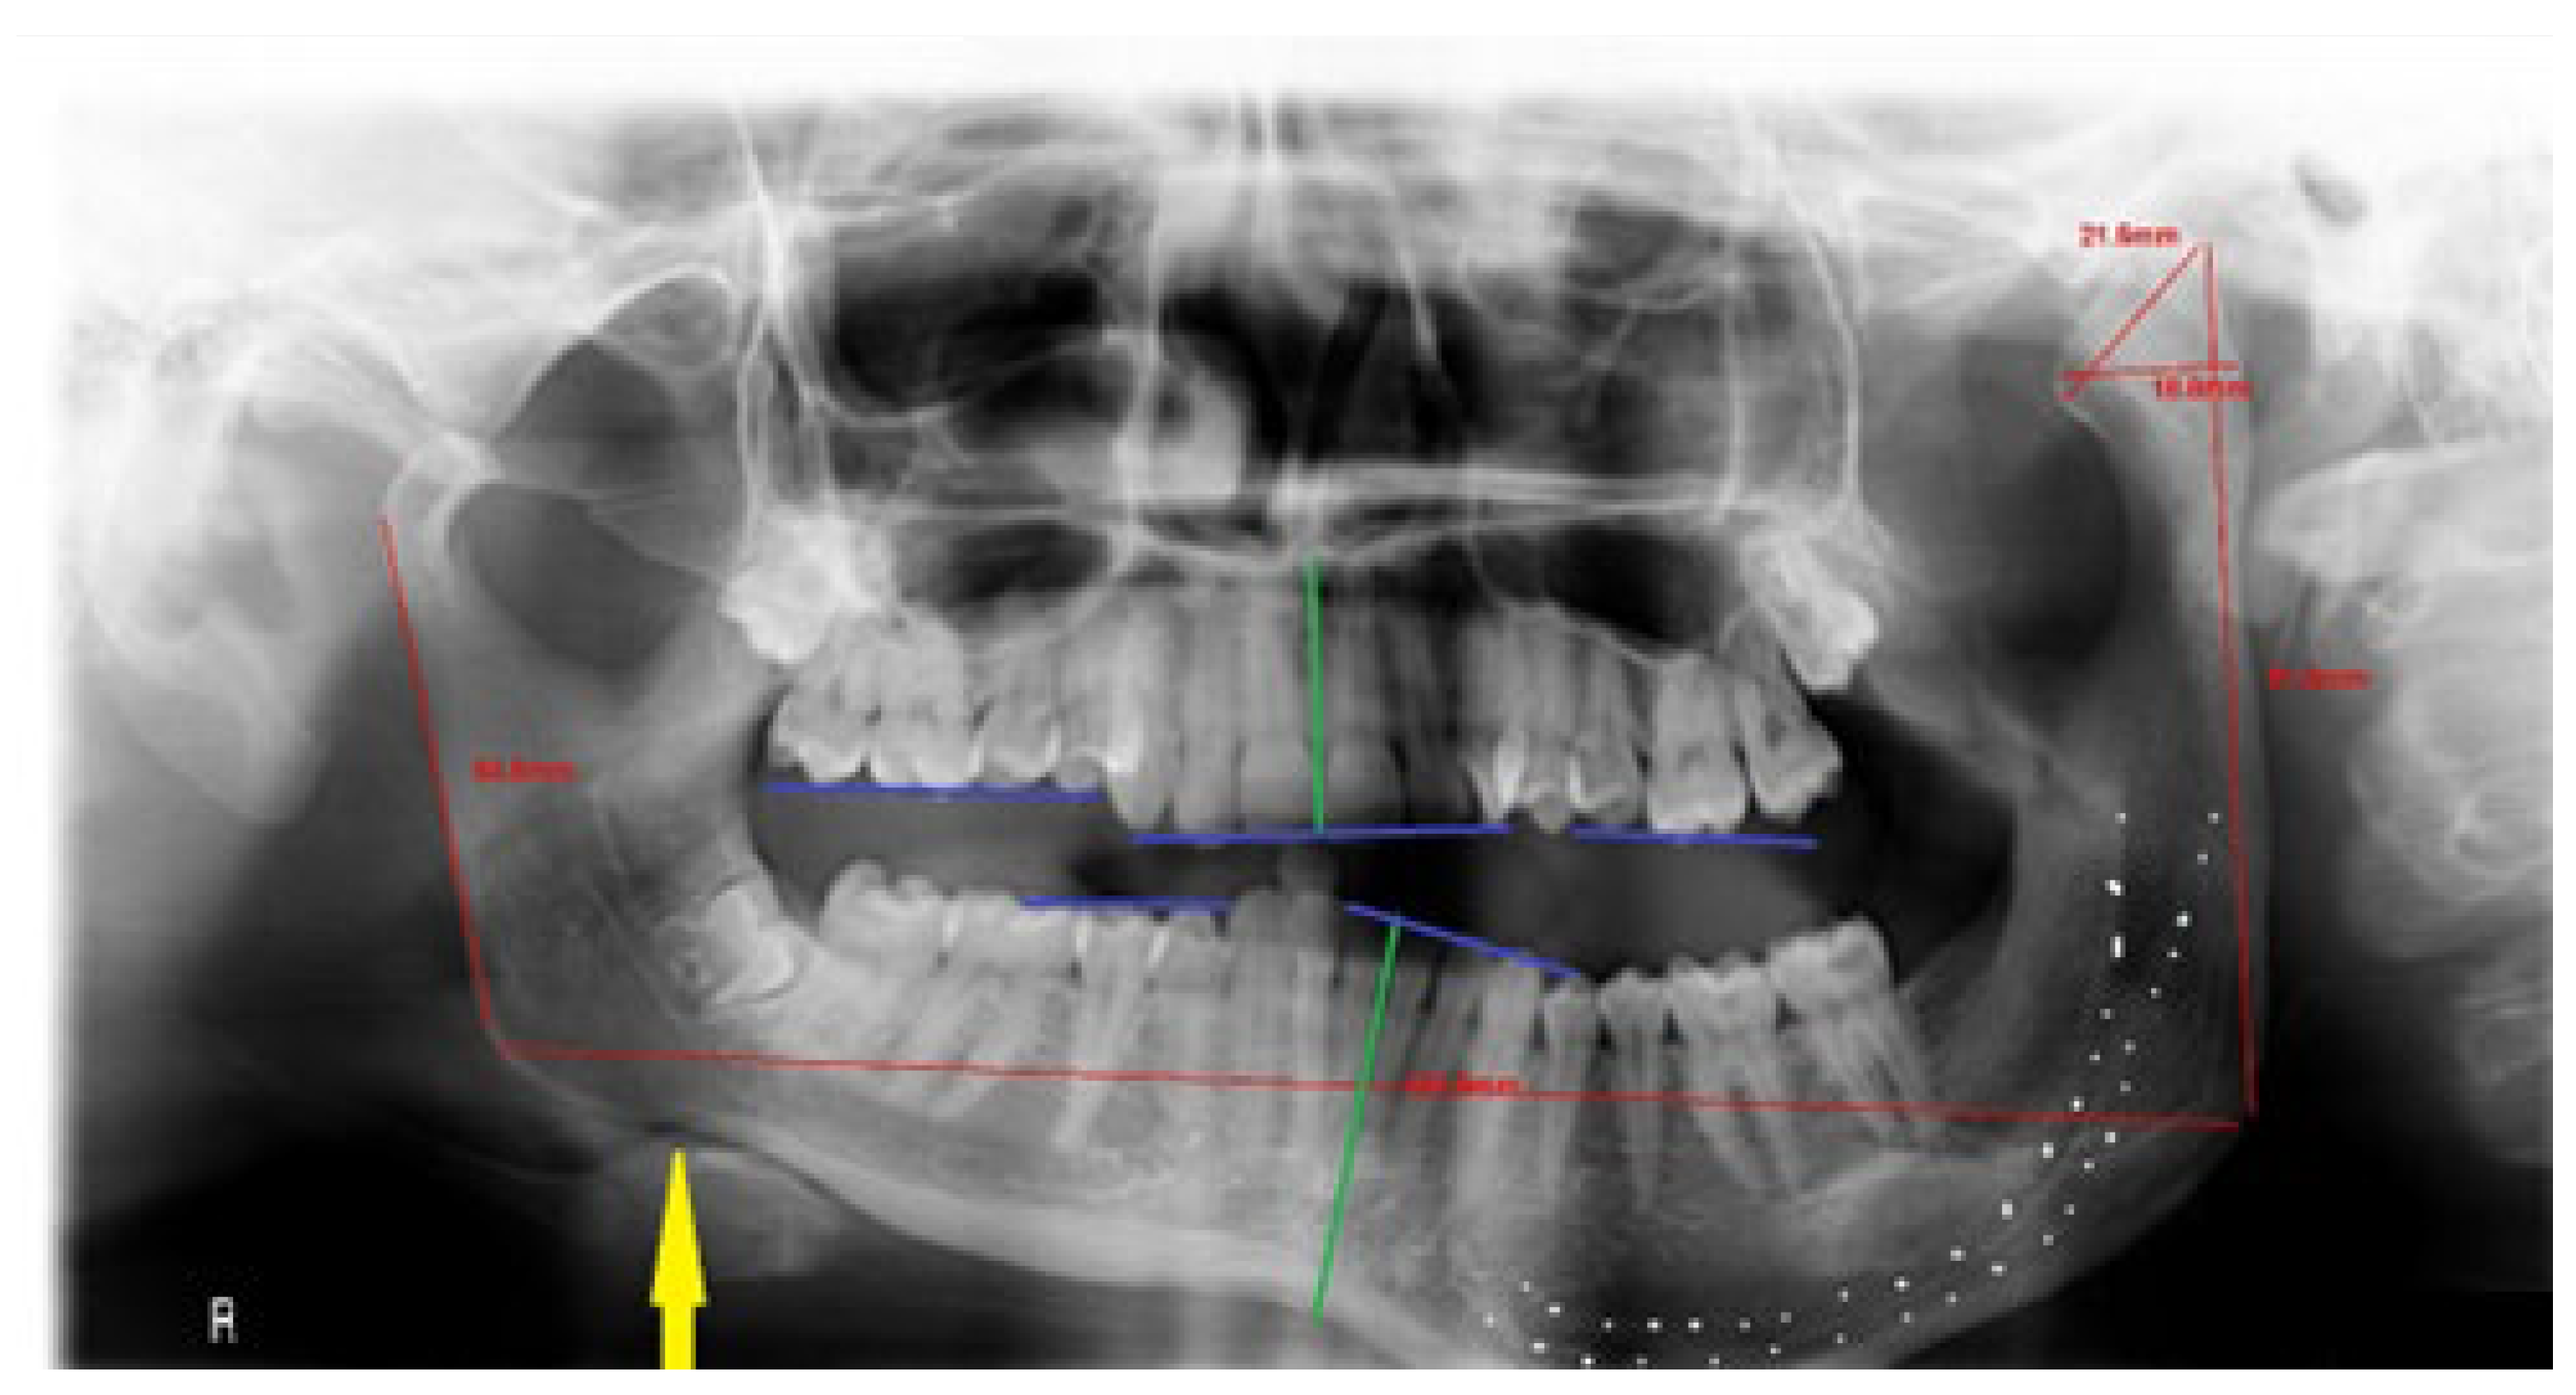

M—maxillary bones; low downward position of the maxilla on the affected side. Maxillary compensatory down growth = with or without maxillary cant deviated horizontal (transverse) occlusal plane (Figure 3), also manifested as the asymmetrical position of part of the maxillary bone with or without sinus floor;

R—ramus vertical height increased (Figure 6)—the distance from the top of condyle head to gonial angle increased, typical for HH cases;

Figure 3. Maxillary compensatory down growth on the affected side.

Figure 6. The increased vertical dimension of the mandibular ramus.